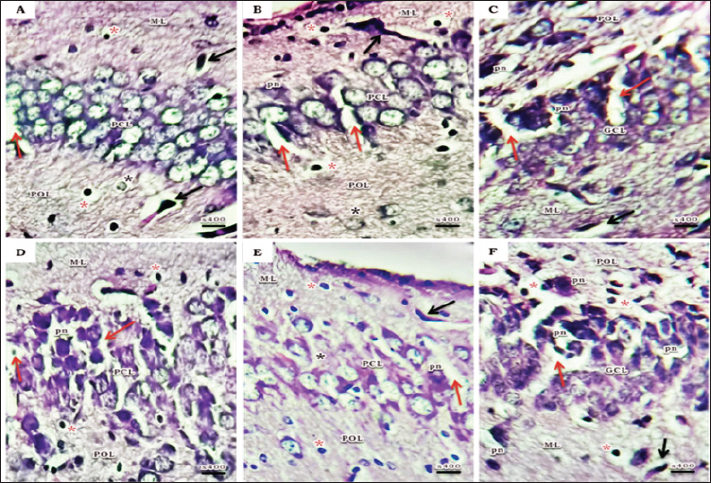

The present study manifested abnormal structural organization of the hippocampus of a 15-day postnatal offspring of both a pre-pregnancy underweight and overweight mother (Figs. 3 and 4), concerning offspring of a pre-pregnancy underweight mother; gender showed varying degrees of histopathological appearance resembling in CA1 region exhibits disorganized pyramidal neurons with dark, shrunken, pyknotic nuclei, and degenerated neurons in pyramidal cell layer, many lightly and deeply stained glial cells nuclei with pericellular haloes and dilated blood capillaries noticed in polymorphic and molecular layers, also CA3 region reveals lightly stained pyramidal cells cytoplasm, few with pyknotic nuclei and some degenerated with vacuoles space in pyramidal cell layer; many deeply stained glial cells nuclei with pericellular haloes and dilated blood capillaries in polymorphic and molecular layers, and DG region displays disorganized dark shrunken granule cell bodies having pyknotic nuclei with pericellular vaculation in granular layer, many deeply stained glial cells nuclei with pericellular haloes and dilated blood capillaries in polymorphic and molecular layers were noticed (Fig. 3). On the other hand, hippocampus of a 15-day postnatal offspring of a pre-pregnancy overweight mother; CA1 region exhibits somewhat regularly arranged pyramidal cell bodies in pyramidal cell layer in female and loosely packed in male offspring, few of them are shrunken with pyknotic nuclei with pericellular vaculation and the others are apparently normal; few lightly and deeply stained glial cells nuclei with pericellular haloes and blood vessel with perivascular halo in polymorphic and molecular layers were noticed, also CA3 region showed few large lightly stained nuclei pyramidal cells, few normal pyramidal cells and some degenerated neurons in pyramidal cell layer, few lightly and many deeply stained nuclei of glial cells with wide pericellular space and dilated blood vessel with wide perivascular halo observed in polymorphic and molecular layers, and DG region displays few dark granule cell with pyknotic nuclei and some degenerated neurons with vacuoles space in GCL, polymorphic and molecular layers exhibit some deeply stained glial cells nuclei with pericellular haloes, dilated and congested blood vessel with wide perivascular halo as well (Fig. 4).

Fig. 3. A photomicrograph of a histological section of the hippocampus of a 15-day postnatal offspring of a pre-pregnancy underweight mother. (A-C) Female offspring and (D-F) Male offspring showing abnormal structure, (A&D) CA1 region exhibits few layers of pyramidal neurons in (A), disorganized with dark, shrunken, pyknotic nuclei (pn) in (D) and degenerated neurons (red arrow) in PCL; many lightly (black star) and deeply (red star) stained glial cells nuclei with pericellular haloes and dilated blood capillaries (black arrow) can be noticed in POL and ML. (B& E) CA3 region reveals lightly stained pyramidal cells cytoplasm (black star), few with pyknotic nuclei (pn) and some degenerated with vacuoles space (red arrow) in PCL; many deeply stained glial cells nuclei with pericellular haloes (red star) and dilated blood capillaries (black arrow) in POL and ML. (C& F) DG region displays disorganized dark shrunken granule cell bodies having pyknotic nuclei (pn) with pericellular vaculation (red arrow) in GCL; many deeply stained glial cells nuclei with pericellular haloes (red star) and dilated blood capillaries (black arrow) can be seen in POL and ML. H&E. Abbreviations; CA1, Cornu Ammonis 1; CA3, Cornu Ammonis 3; DG, Dentate Gyrus; GCL, granular layer; ML, Molecular layer; PCL, Pyramidal cell layer; POL, Polymorphic layer.